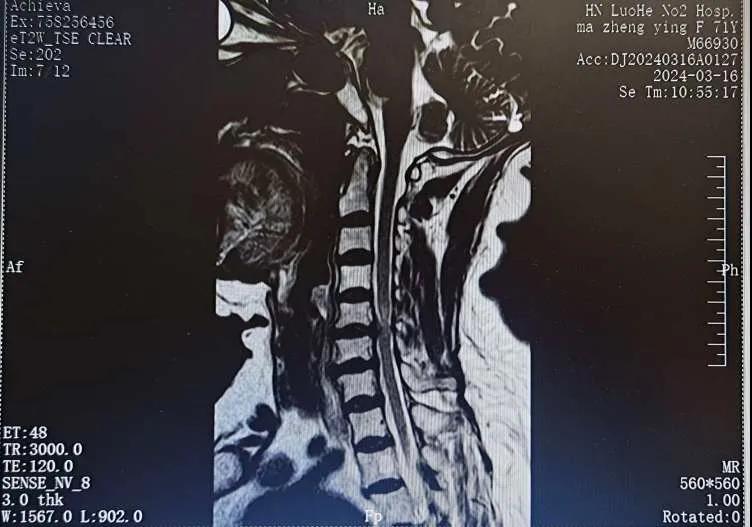

近日,70歲的馬阿姨,因摔傷后出現持續性頸部疼痛伴右側肢體無力、麻痛,影響日常生活。于是來到市二院神經外科就診,經檢查發現:頸椎MR示:頸3/4、4/5、5/6、6/7椎間盤變性突出(中央型)并繼發性椎管變窄,頸椎退行性改變,頸5椎體水平頸髓水腫。神經外科副主任劉沛濤根據患者癥狀、體征、影像學三者結合診斷為“脊髓型頸椎病”,考慮到患者癥狀逐漸加重、保守治療效果不佳等情況,建議盡快手術治療。

經過縝密的術前準備和手術計劃,在鄭大一附院神經外科張風江教授的指導下,神經外科團隊順利為患者實施“顯微鏡下頸椎前路C5/C6椎間盤切除椎間融合+內固定術”,手術時間不到1小時。術后患者恢復情況良好。